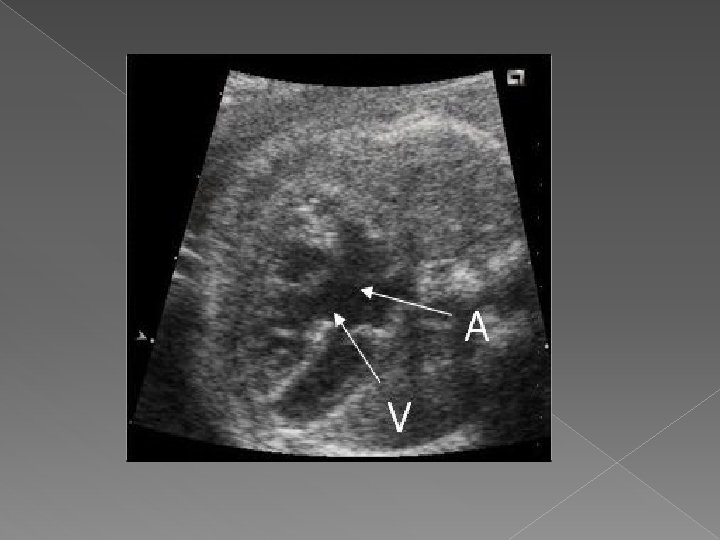

Other Cardiac Anomalies Some other conditions that can be diagnosed using ultrasound: Endocardial Cushion Defects › Atrial and ventricular septal defects resulting from failure of the common AV orifice to separate into mitral and tricuspid valves. Associated with an increased risk of Trisomy 21. Tetralogy of Fallot › Consists of four anatomic abnormalities: Large VSD, overriding aorta, pulmonary infundibular stenosis, right ventricular hypertrophy. Ebstein’s Anomaly � Downward displacement of the septal and posterior leaflets of the tricuspid valve

� Endocardial cushion defect is also called atrioventricular septal defect (AVSD). AVSD involves problems with the structure of the heart. The heart normally has 2 upper chambers (atria) and 2 lower chambers (ventricles). A normal heart also has 2 heart valves (the tricuspid and mitral valves) that separate the upper and lower chambers.

� In AVSD, there may be a large hole in the center of the heart where the wall (septum) joins the upper and lower chambers of the heart. The tricuspid and mitral valves may not be separate. Instead, there can be one large valve between the upper and lower chambers of the heart (common atrioventricular valve). The large opening in the center of the heart allows the oxygen-rich (red) and the oxygen-poor (blue) blood to mix. The heart pumps blood in a way that is not efficient and becomes enlarged.

An AVSD is the most common congenital heart defect found in children with Down's Syndrome, accounting for 50% of the total. � In its complete form there is a hole in the wall between the top chambers (atria) and a hole in the wall between the bottom chambers (ventricles), and one common valve between the two atria and the two ventricles. In the partial forms there may not be a hole between the bottom chambers (ventricles) or the mitral and tricuspid valves may not be joined together, but either or both may leak, known as valve incompetence. �